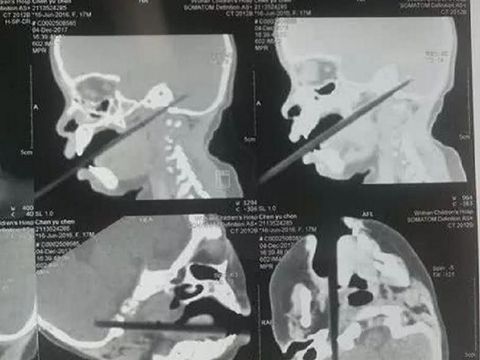

Chenchen langsung dilarikan ke rumah sakit di mana dokter segera memeriksa melalui CT scan padanya. Tim dokter kemudian mengatur agar ia menjalani operasi dengan cepat. Dokter mengungkapkan bahwa 2 cm dari sumpit tersebut telah menusuk cerebellumnya atau bagian dari otak yang bertanggungjawab untuk gerakan motorik. Sumpit juga menembus area vena jugularis interna yang bertanggungjawab mengalirkan darah dari otak, wajah bagian dalam dan leher.

Menurut dokter Chenchen cukup beruntung sumpit itu tidak sampai menembus ke batang otaknya. Kalau sampai terjadi nyawanya sulit diselamatkan.